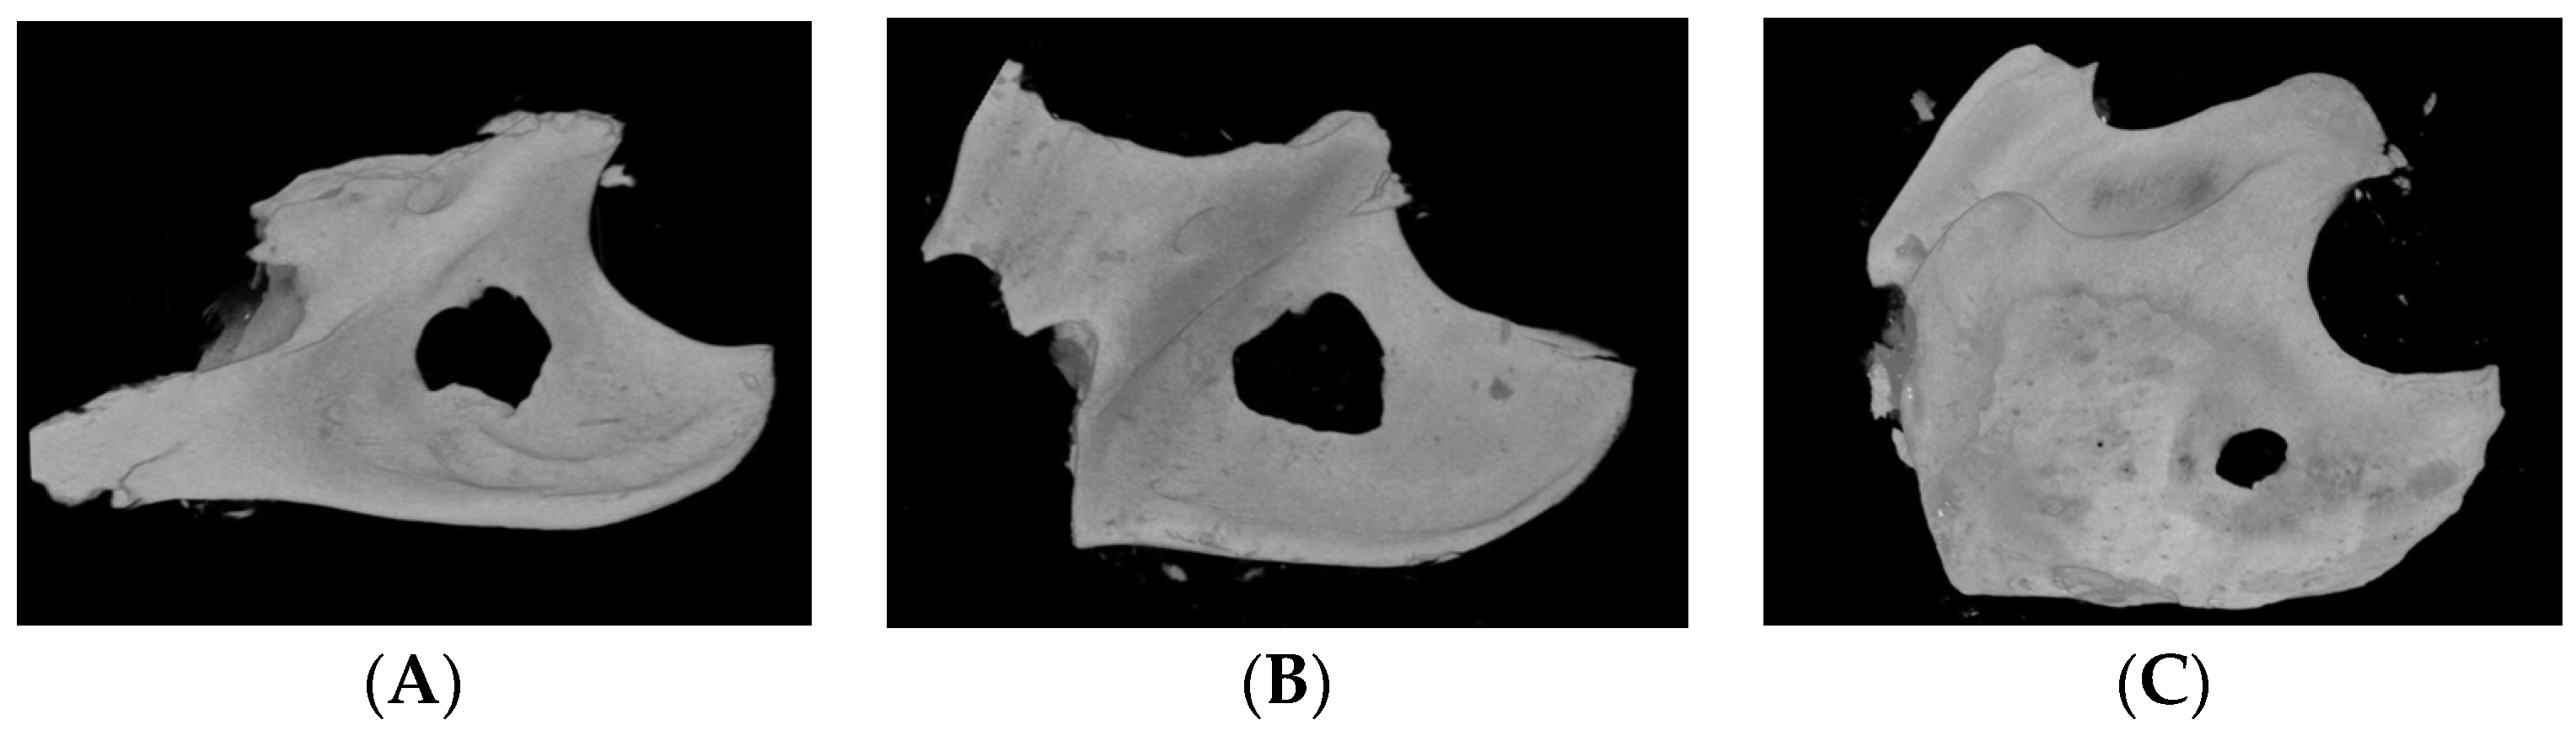

The sagittal images of the mandible bone defect of the μ-CT in each group are presented in Figure 2. The round bony defect was created, and the newly formed bone was observed at each end of the defect in the three groups. Especially, remarkable bony calcification was observed in the bone defects of the 10 M and 20 M groups. In the 10 M group, the newly formed bone was connected to each of the end edges of the defect, making a bony bridge across the defect (Figure 2B). And thick and calcified new bone was observed at the end edge in the defect of the 20 M group (Figure 2C).

Figure 2. The sagittal images of the micro-computed tomography of the mandible bone defect of (A) 2 M, (B) 10 M, and (C) 20 M groups. The new bone regeneration was observed from the edge of the bone defect.